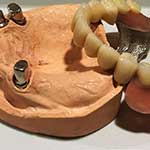

Γενικότερα, η προσθετική δοντιών είναι ο οδοντιατρικός τομέας που ασχολείται με τον σχεδιασμό και την εφαρμογή κατασκευών, οι οποίες αναπληρώνουν τα δόντια που λείπουν με τεχνητά δόντια.

Στην ακίνητη προσθετική χρησιμοποιούνται ειδικές θήκες (ή στεφάνες ή κορώνες) ή γέφυρες. Η θήκη είναι ουσιαστικά ένα καλύμματα σε σχήμα δοντιού. Η θήκη αυτή τοποθετείται σε ένα δόντι το οποίο έχει διαμορφωθεί κατάλληλα έπειτα από τρόχισμα που του κάνει η οδοντίατρος. Η γέφυρα είναι μία κατασκευή που αντικαθιστά ένα ή περισσότερα δόντια και στηρίζεται στα διπλανά δόντια (δόντια-στηρίγματα).

ΚΙΝΗΤΗ ΠΡΟΣΘΕΤΙΚΗ

Κινητή Προσθετική

Όταν αναφέρεται ο όρος κινητή προσθετική δοντιών, γίνεται λόγος για τις γνωστές τεχνίτες οδοντοστοιχίες (μασέλες). Οι οδοντοστοιχίες αυτές μπορεί να είναι ολικές και χρησιμοποιούνται όταν για διάφορους λόγους έχουν χαθεί όλα τα δόντια του ασθενή, ή μερικές, στην περίπτωση που έχουν χαθεί αρκετά δόντια άλλα όχι όλα.